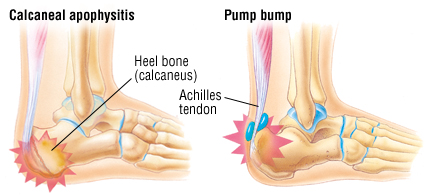

PhysioPoint.ie pain in the back of the heel

Heel Spurs - The Foot Care Group Deformity and Other Causes of Heel Pain

Deformity and Other Causes of Heel Pain  Plantar Fasciitis: The Complete